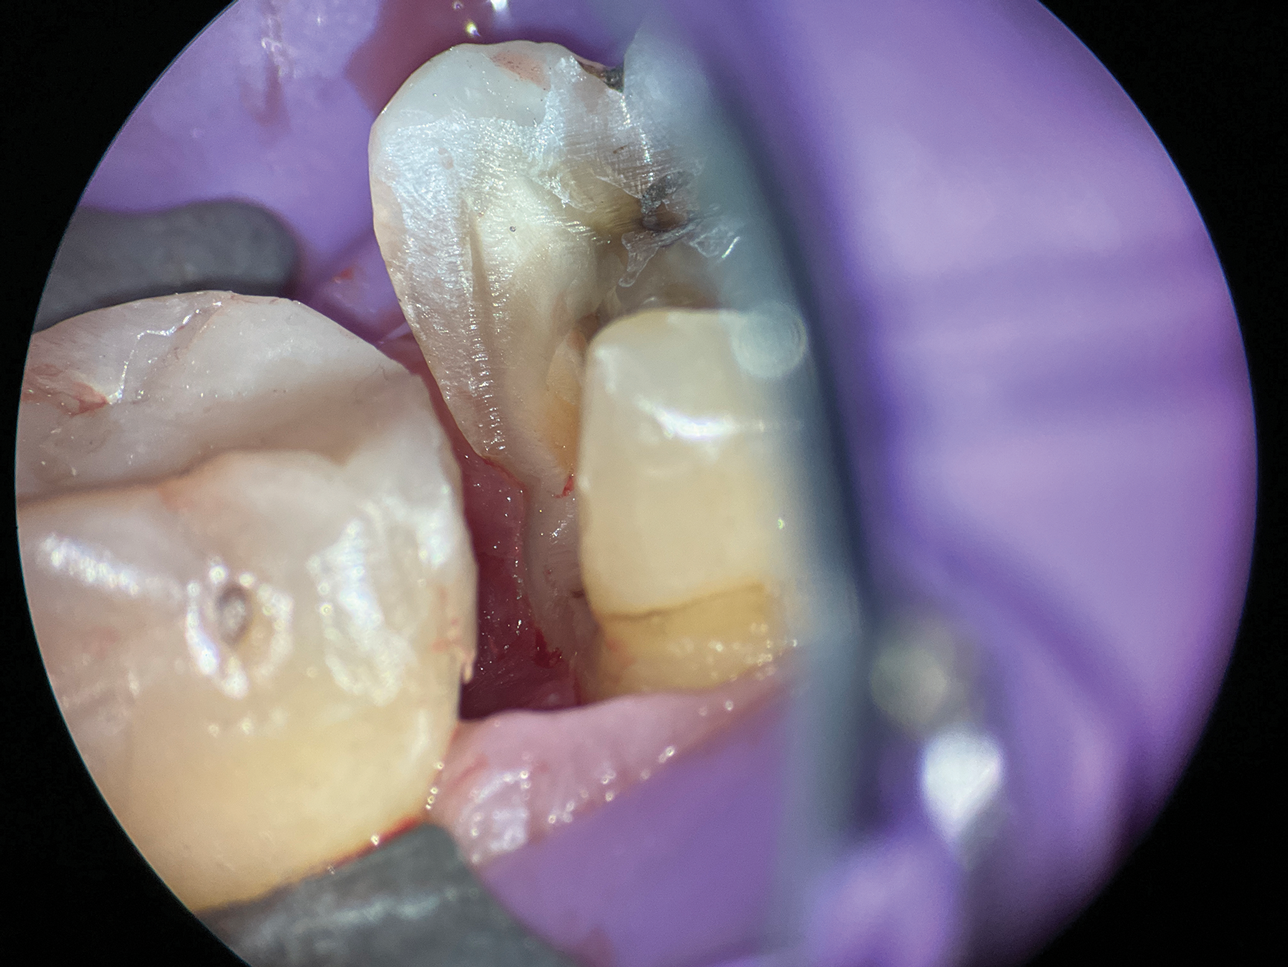

When cavity margins are located in the canine fossa due to caries, fractures, or cracks, the unique anatomy of this concavity poses a significant challenge (Figure 2 and Figure 3). Conventional matrix systems often fail to conform to its complex form and angles. This requires practitioners to possess expertise in adapting a customized matrix to suit the intricate contours of the fossa.

With its malleability and adaptability, a copper band offers an unparalleled solution for this purpose. It allows the practitioner to cut and shape the band to precisely match the unique structure of the canine fossa, accommodating variations in form and angles (Figure 4). Using a thicker copper band (ie, approximately 5 mil), provides the necessary strength to maintain stability during treatment. In addition, it effectively retracts the gingival tissue, which facilitates the placement and contouring of restorative materials, such as composite (Figure 5 and Figure 6).

(2.) Close-up occlusal view of a maxillary first premolar during restorative treatment revealing a mesial structural crack.

Figure 2

(3.) Close-up occlusal view of the maxillary first premolar after removal of the thin cusps and dissection of the mesial crack, which resulted in a subgingival margin.

Figure 3

(5.) Close-up occlusal view of the modified copper band placed to isolate the margin during deep margin elevation and stabilized with a wedge and a piece of polytetrafluoroethylene tape.

Figure 5